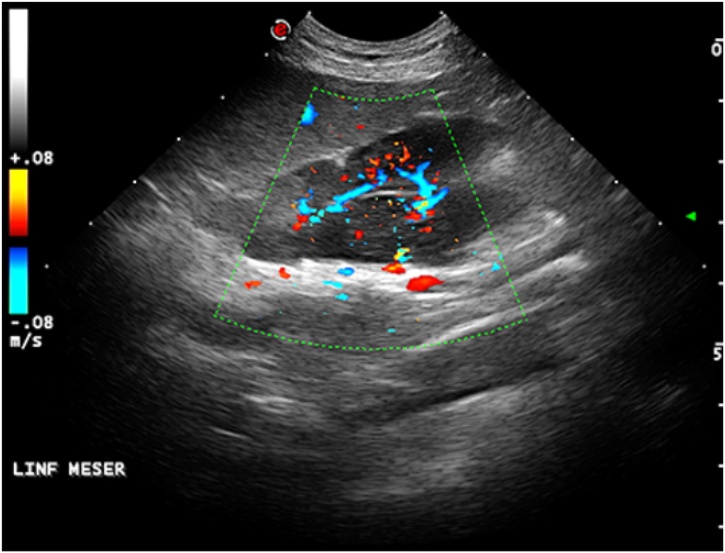

Lymph nodes ultrasonography is frequently performed in different anatomical regions and so it is for the abdomen. Their evaluation may rise suspect of the presence of malignant disease or inflammatory conditions. Lymph nodes ultrasonographic features as shape, vascularity, echogenicity helps in the diagnosis of the ongoing disease (Fig. 15) [41,42].

Fig. 15.

Lymphoma in a 9-years old male Domestic cat. Enlarged hypoechoic abdominal lymph node with a mixed hilar and peripheral blood supply.